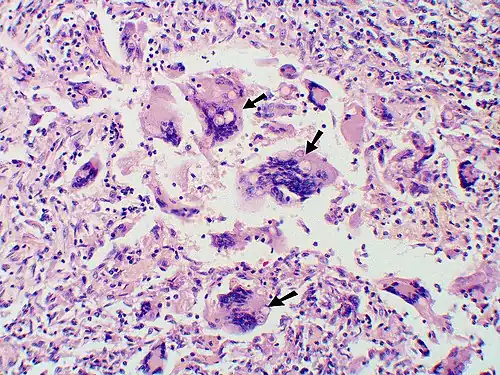

Granuloma with early suppuration. The fungal organisms are difficult to recognize at this low magnification. -

Large yeast-like fungi seen within giant cells at arrows. -

Large yeast-like fungi seen within giant cells at arrows. Budding yeasts in the cytoplasm of giant cells at the arrows. Broad-based budding and double-contoured cell walls are seen in the giant cell in the center are characteristic of Blastomyces dermatitidis. -